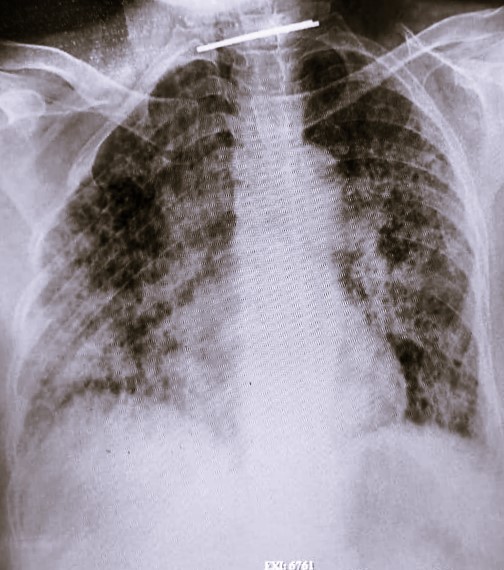

| 340 | IGGMC, Nagpur, Nagpur | P2 | 29-4132 | Ajay Dhabne | Consent taken on Paper | 44 Yrs. |

Provisional Diag : ILD (Interstitial Lung Disease)

Final Diag : ILD In Exacerbation With Old Treated Pulmonary TB With Post Covid Satiation |

Result awaited (Suspected TB/Non-TB) | Abnormality visible on x-ray |